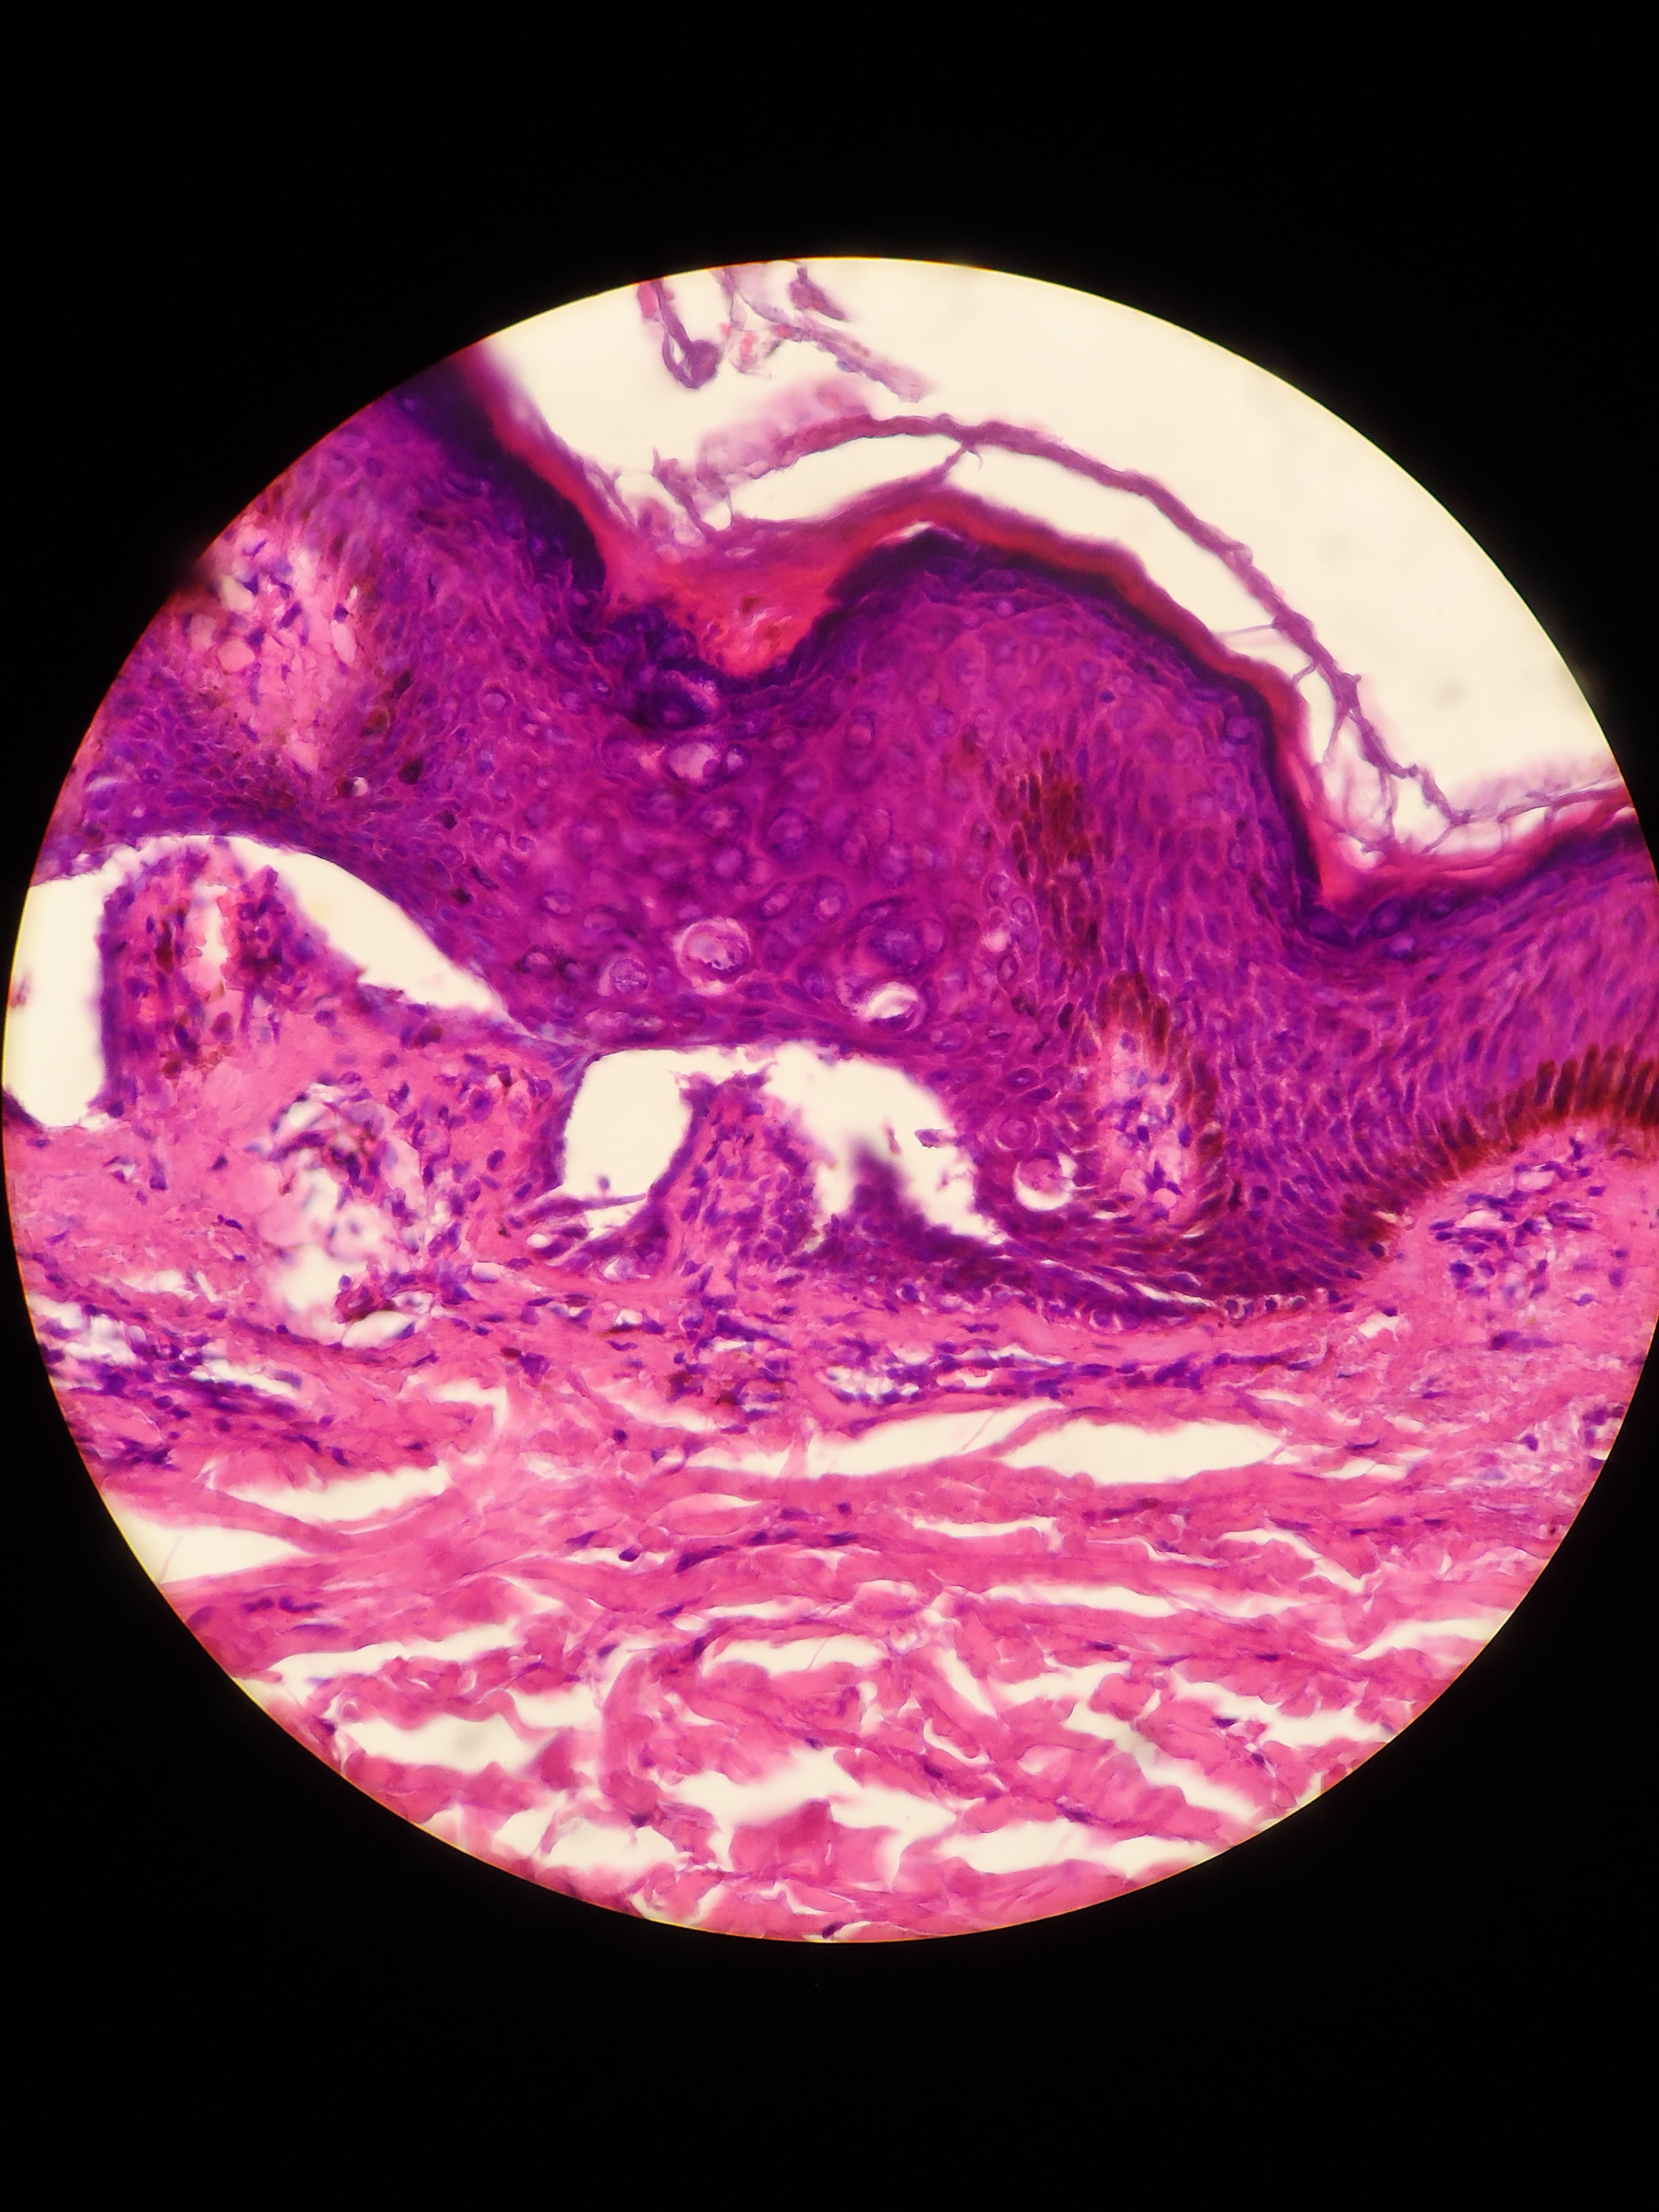

ENFEREMEDAD DE DARIER - HISTOPATOLOGIA